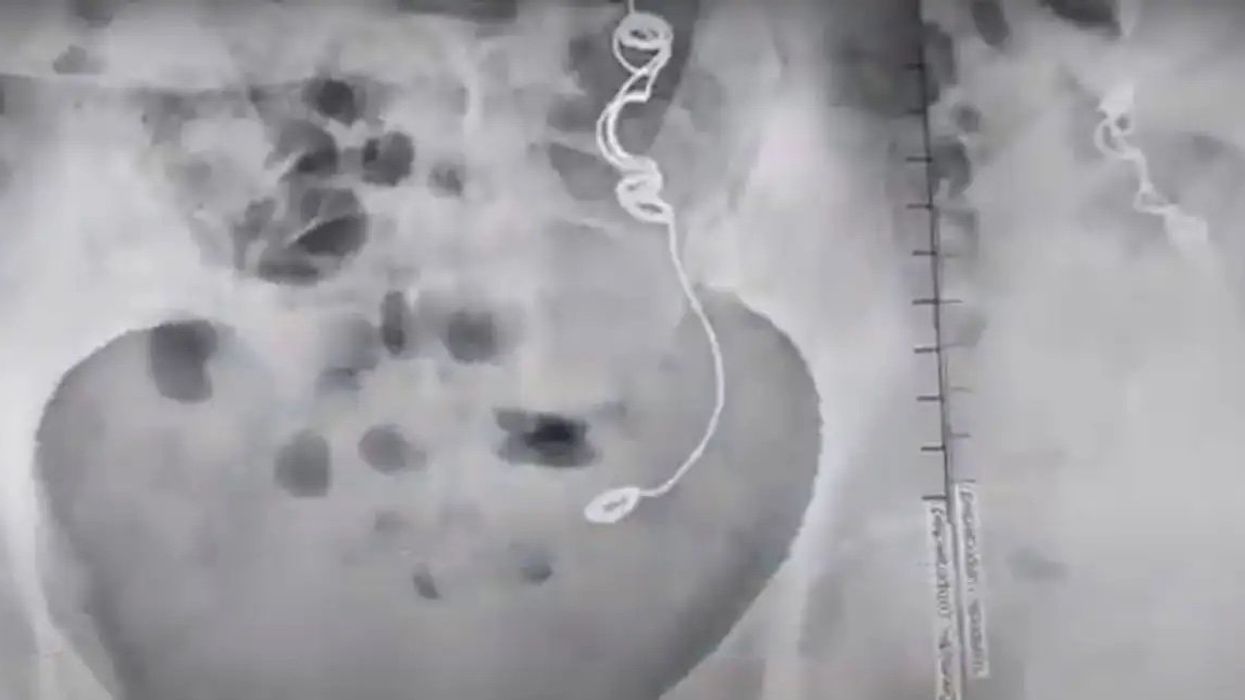

But the needle and thread were accidentally left there after the surgery in 2012.

Her condition was eventually diagnosed when an ultrasound and MRI scan showed the cause of her pain, leaving María and the doctors stunned.

She had apparently spent over 4,000 days in pain due to the needle and thread being left in her body.